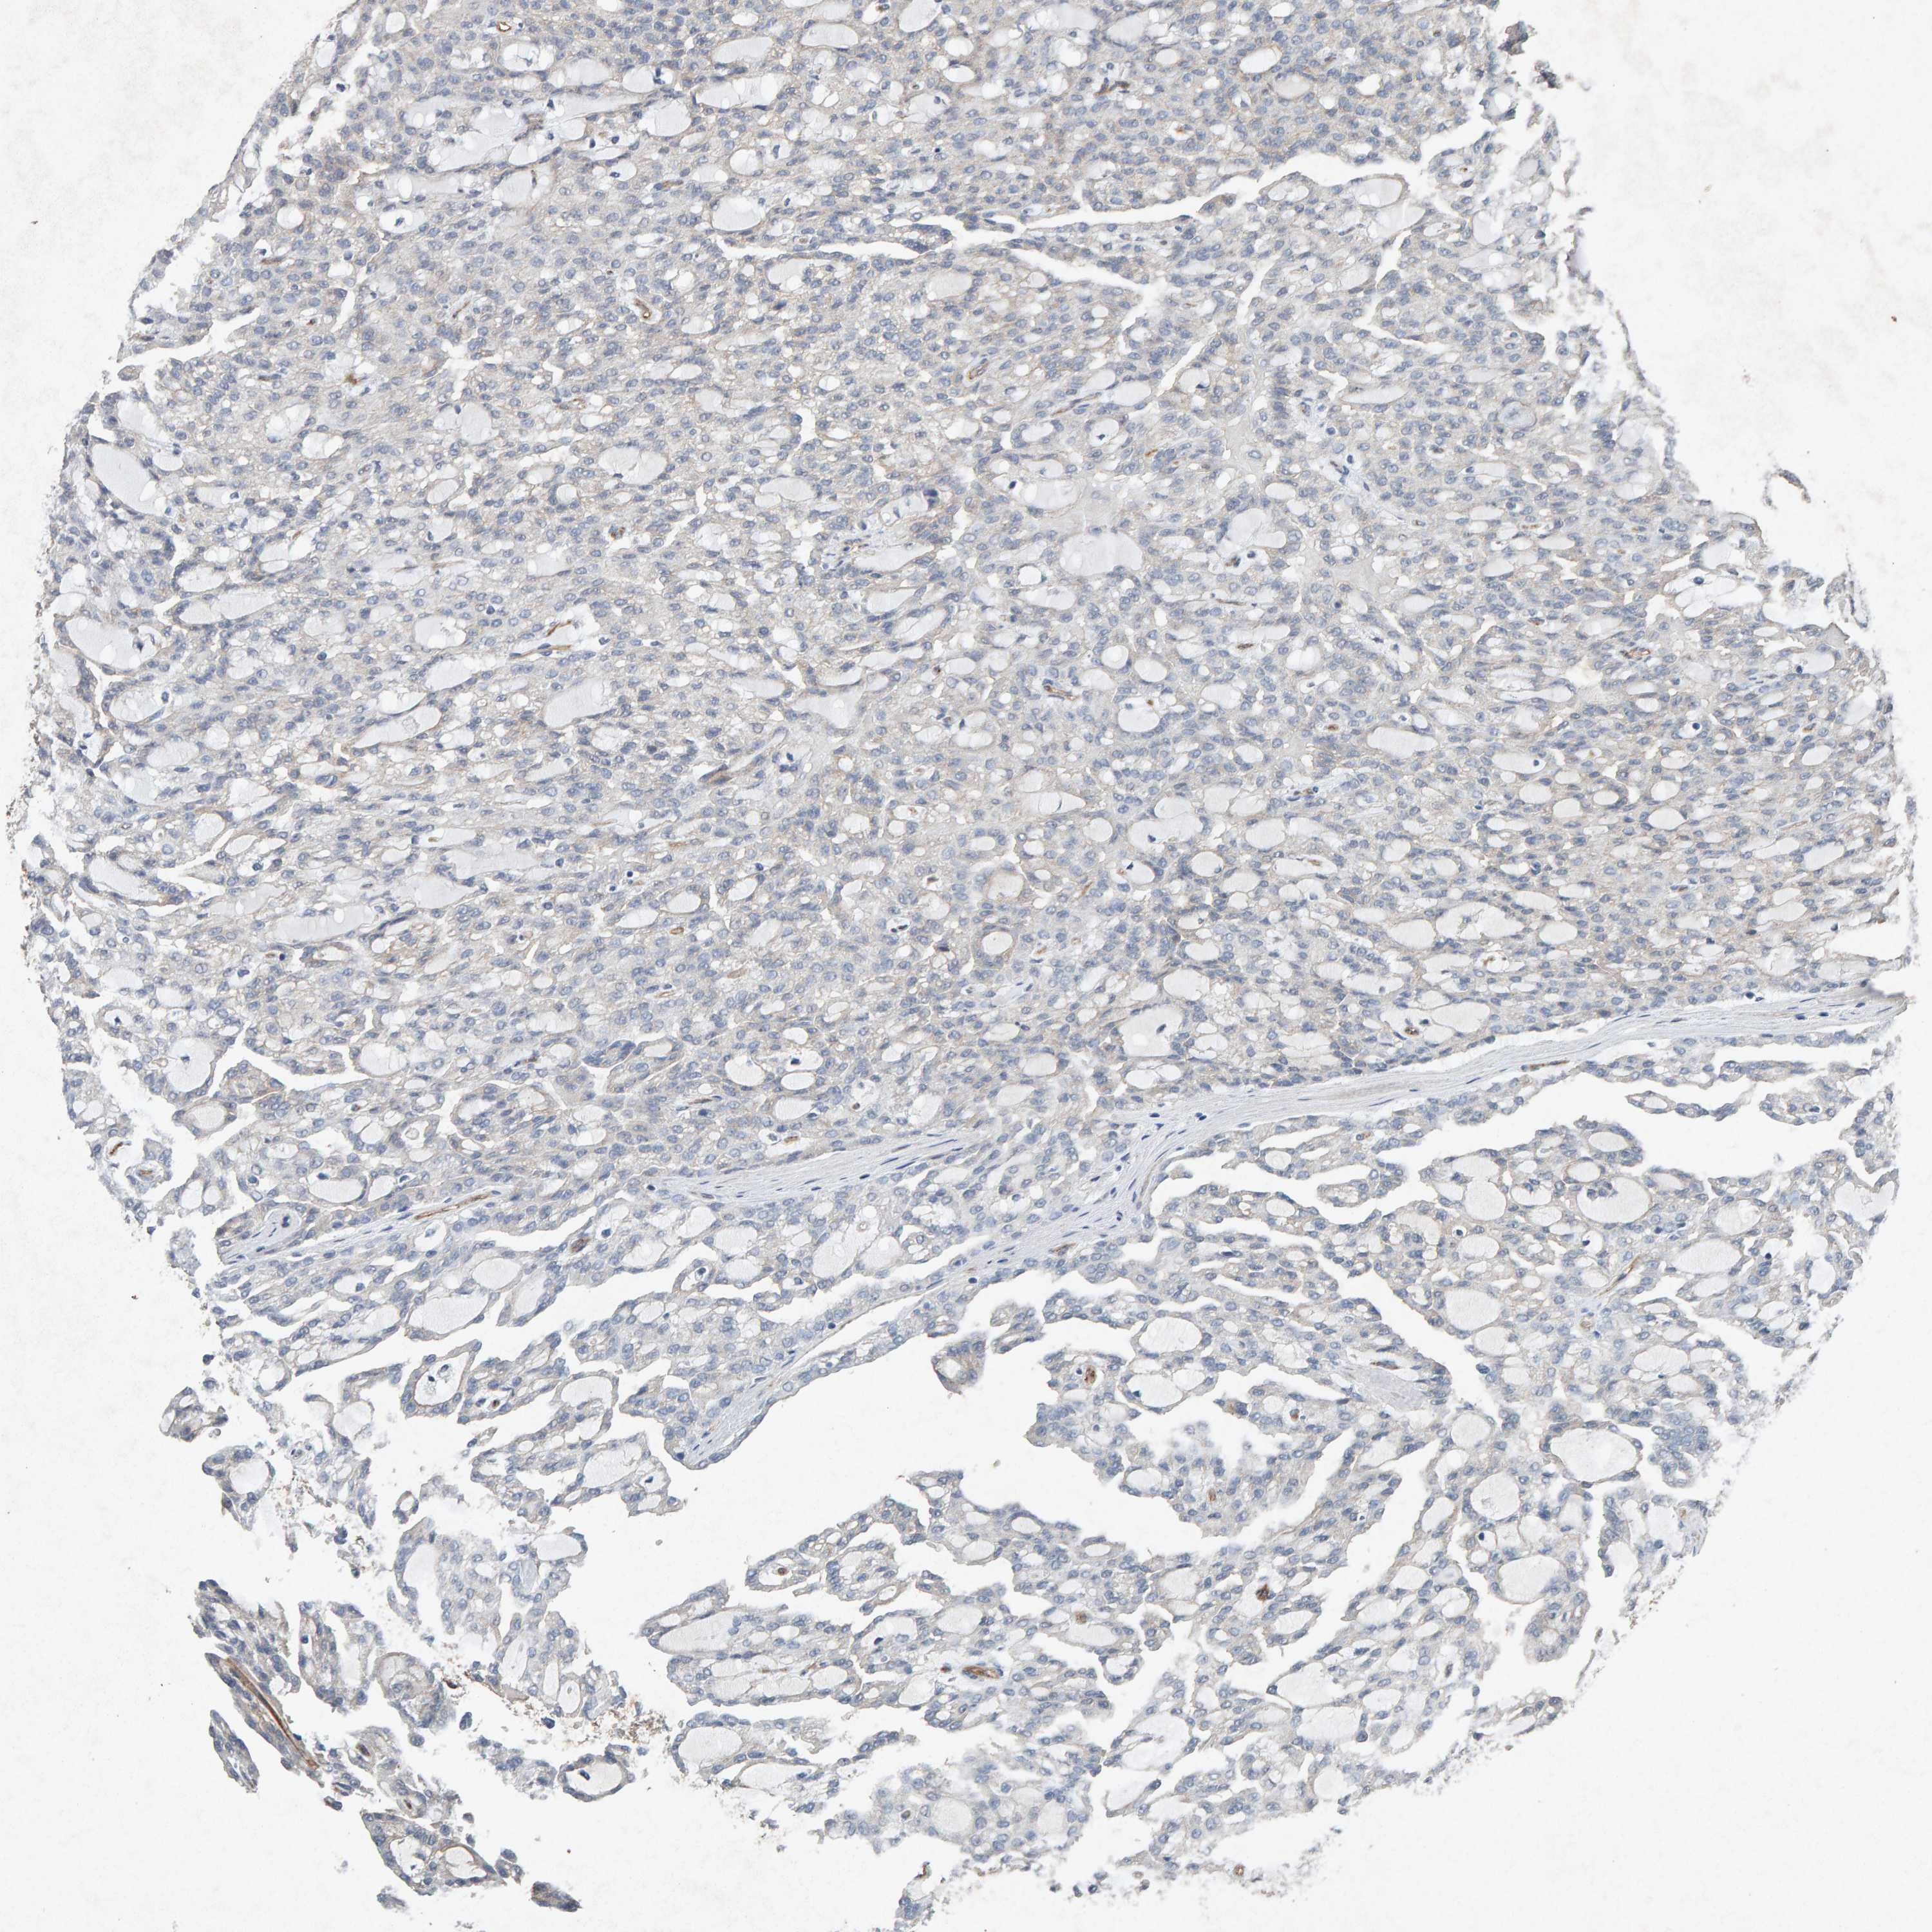

KIDNEY RENAL PAPILLARY CELL CARCINOMA (TCGA) - Interactive survival scatter ploti

The Survival Scatter plot shows the clinical status (i.e. dead or alive) for all individuals in the patient cohort, based on the same data that underlies the corresponding Kaplan-Meier plots. Patients that are alive at last time for follow-up are shown in blue and patients who have died during the study are shown in red.

The x-axis shows the expression levels (FPKM) of the investigated gene in the tumor tissue at the time of diagnosis. The y-axis shows the follow-up time after diagnosis (years). Both axes are complimented with kernel density curves demonstrating the data density over the axes. The top density plot shows the expression levels (FPKM) distribution among dead (red) and alive patients (blue). The right density plot shows the data density of the survived years of dead patients with high and low expression levels respectively, stratified using the cutoff indicated by the vertical dashed line through the Survival Scatter plot. This cutoff is automatically defined based on the FPKM cutoff that minimizes the p-score. The cutoff can be changed by dragging the vertical line or by entering a cutoff value in the square labeled "Current cut-off".

Under the Survival Scatter plot the p-score landscape (black curve; left axis) is shown together with dead median separation (red curve; right axis). Dead median separation is the difference in median mRNA expression between patients who have died with high and low expression, respectively. It is calculated as follows: median FPKM expression of dead patients with high expression - median FPKM expression of dead patients with low expression. This is intended to aid the user in visually exploring custom cutoffs and the associated p-scores and dead median separation.

Individual patient data is displayed and can be filtered by clicking on one or more of the category buttons on the top of the page. Categories describing expression level and patient information include: high, low, alive, dead, female, male and tumor stages. The scale of the x-axis can be toggled between linear and log-scale by clicking on the "x log" button. Mouse-over function shows TCGA ID, patient information and mRNA expression (FPKM) for each patient.

& Survival analysisi

Kaplan-Meier plots summarize results from analysis of correlation between mRNA expression level and patient survival. Patients were divided based on level of expression into one of the two groups "low" (under cut off) or "high" (over cut off). X-axis shows time for survival (years) and y-axis shows the probability of survival, where 1.0 corresponds to 100 percent.

PTPRM is not prognostic in Kidney Renal Papillary Cell Carcinoma (TCGA)